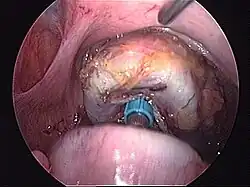

- Schematyczne obrazy jelita grubego i uchyłków esicy i śródoperacyjne obrazy uchyłków i nowotworu jelita grubego

Śródoperacyjny widok uchyłków esicy (operacja laparoskopowa).

Śródoperacyjny widok nowotworu esicy (operacja laparoskopowa).

- Dolna granica resekcji jelita

Dolna granica resekcji esicy w przypadku uchyłkowatości jelita grubego.

Kontynuacja resekcji staplerem liniowym. Resekcja przeprowadzona jest doogonowo od anatomicznej i czynnościowej esiczo-odbytniczej strefy wysokiego ciśnienia.